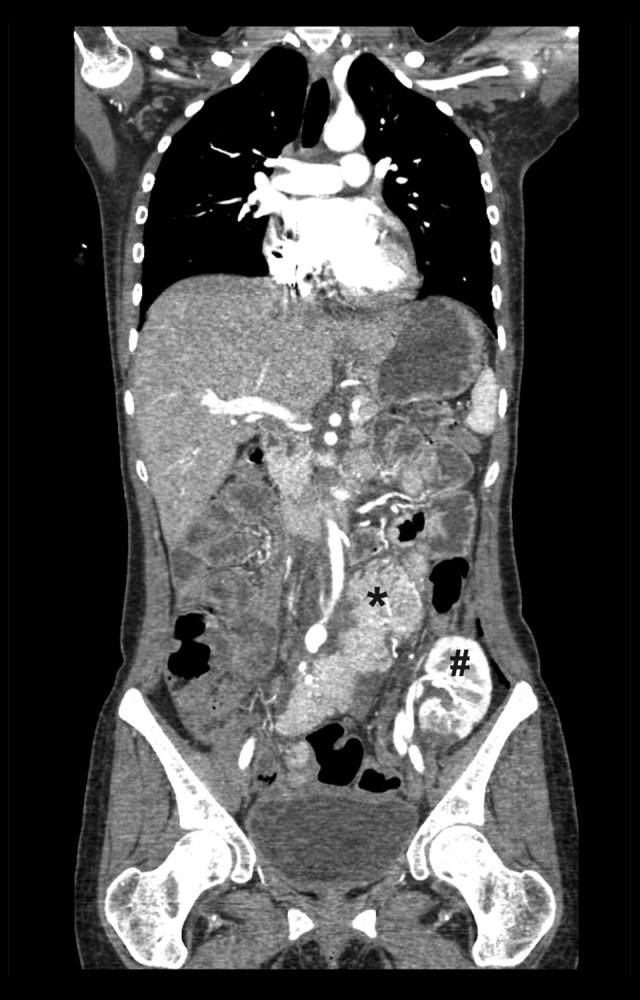

BACKGROUND There has been, to our knowledge, no reports on LifeCycle Pharma tacrolimus (LCPT) taken during pregnancy after simultaneous pancreas-kidney transplantation (SPK). Here, we report a 25-year-old female SPK recipient who gave birth to a healthy infant in posttransplant month 32. We analyzed the long-term graft function, obstetric/neonatal course, LCPT dosage, tacrolimus (TAC) levels, concomitant medication, and complications. CASE REPORT Her medical history consisted of type 1 diabetes with chronic nephropathy, arterial hypertension, and atypical haemolytic uremic syndrome with critical deterioration of her general condition requiring clinically indicated early termination of her first pregnancy prior to SPK. SPK was performed according to surgical standards. The immunosuppressive prophylaxis consisted of thymoglobulin, mycophenolate mofetil, standard TAC formulation, and steroids. Due to rapid TAC metabolism, the patient was converted from a standard TAC formulation to LCPT in the first month posttransplant. Her long-term immunosuppression, including the obstetric and peripartal course, consisted of LCPT, prednisolone, and azathioprine. She was normotensive without antihypertensive medication and maintained excellent function of both grafts during the observation period of 48 months posttransplant. All (mostly infectious) complications were reversible, especially temporary polyoma viremia within normal renal function, and 2 episodes of urosepsis. No relapse of her pretransplant episode of atypical haemolytic uremic syndrome occurred posttransplant. Her child is in good health at the age of 12 months without any malformations. CONCLUSIONS This case suggests that pregnancy after SPK under LCPT is feasible. Further studies are needed to expand the empirical knowledge surrounding tacrolimus.